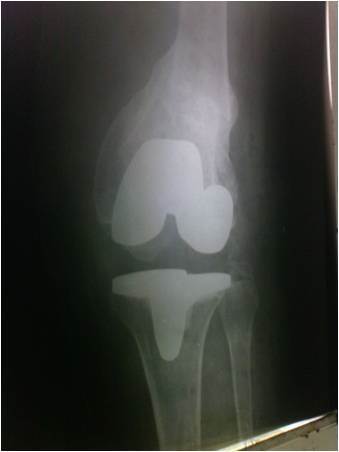

X-ray Before and after the operation

Pre-Operative Plain X-ray